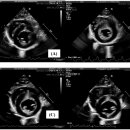

• 한남심장내과동물병원 | 한남심장내과동물병원 강아지 심장초음파 검진 내돈내산 후기

검사, 초음파검사, 혈액검사 proBNP, 혈액검사 Cardiac TnI 등등의 검사를 받고 약 2주 치를 받아서​ 총비용은 781,500원이 나왔습니다 ​ ....😭 ​ 한남심장내과동물병원 검진 후기 검사하고 결과를 듣고 약을 받는 데까지 약 두 시간 정도 소요되었어요​ 그리고 당일에 검진 결과서와 초음파 자료를 정리해서 메일로 전달...

산소포화도가 많이 낮지 않아서 산소를 쐬지 않고 검사를 진행했어요 ​ ​ 심장초음파를 보면서 설명해 주시는 원장님 ​ ​ 저번에 방문해서 처방 받았던 약을 먹고...물도 떠 주셨어요👍🏻 패드는 실수를 할까봐 저희가 깔았답니다! ​ 진심동물내과심장병원 대구광역시 수성구 동대구로 346 서한포레스트 상가동 1층(대로변에서...